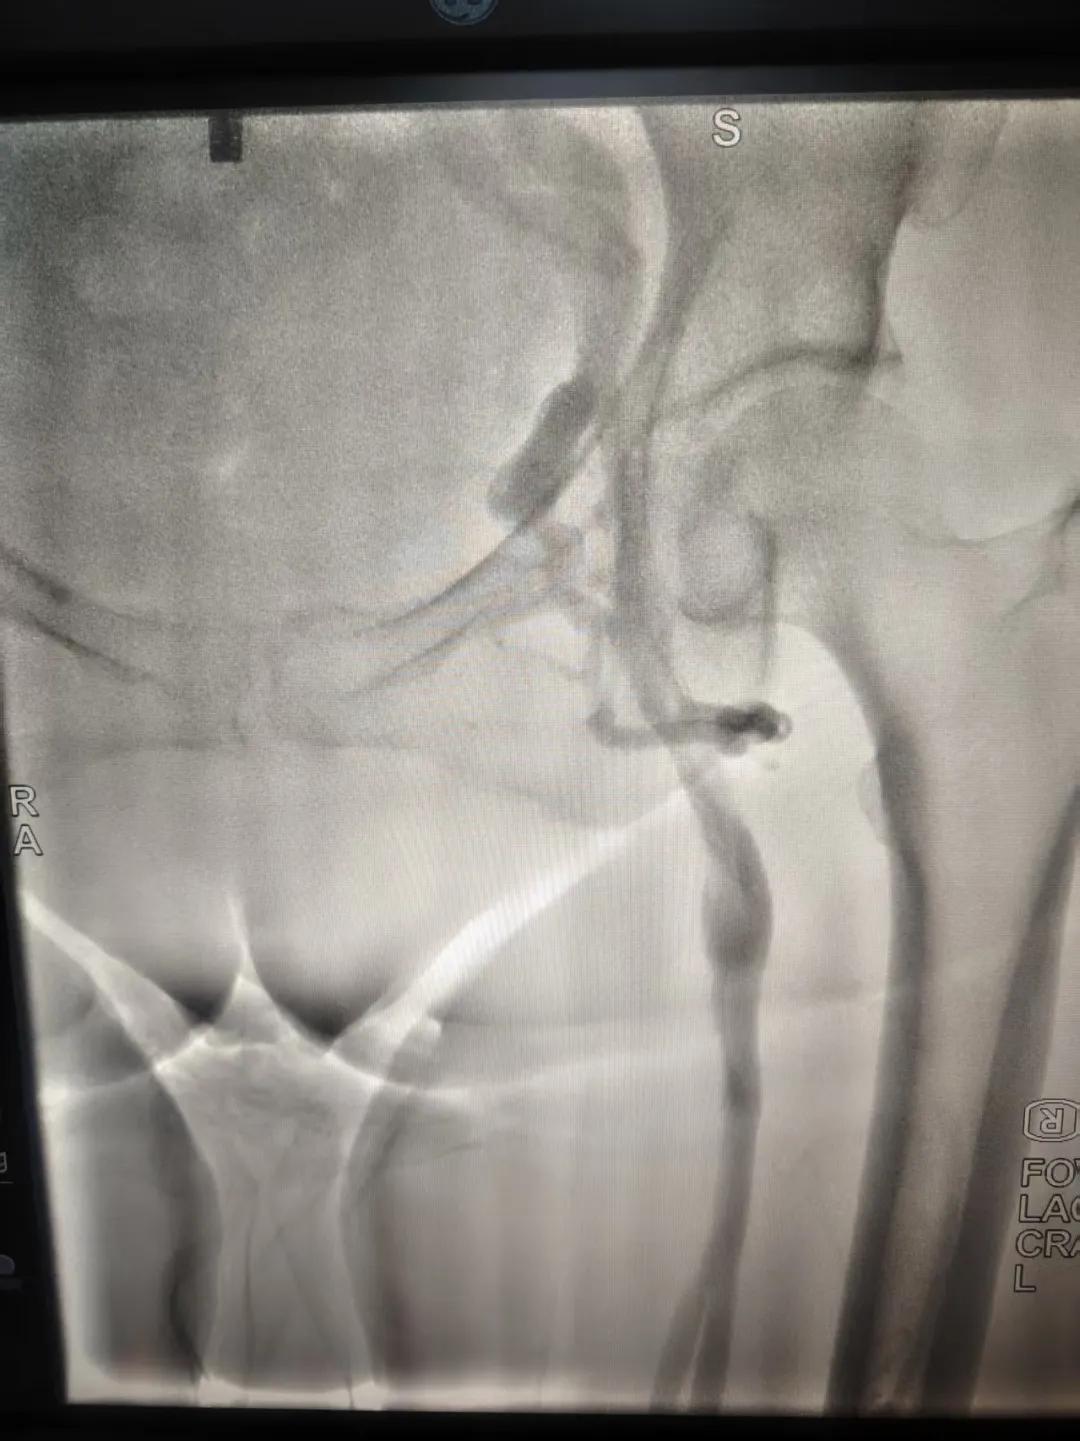

該患者,中年女性,左下肢反復腫脹、疼痛多年就醫,未明病因。門診就診,經血管外科副主任周創業評估病情后,為該患者門診行下肢靜脈造影,造影結果示:左髂靜脈周圍側枝形成,左髂靜脈壓迫綜合癥。明確診斷后將擇期介入手術治療。

下肢靜脈造影是診斷下肢靜脈病變(如深靜脈血栓、靜脈曲張、靜脈功能不全等)的“金標準”。靜脈造影可直觀顯示受壓部位、狹窄程度及側支循環形成情況,明確診斷與定位,指導治療決策,以及介入治療規劃,血栓評估,在復雜病例或介入治療中造影具有優勢。